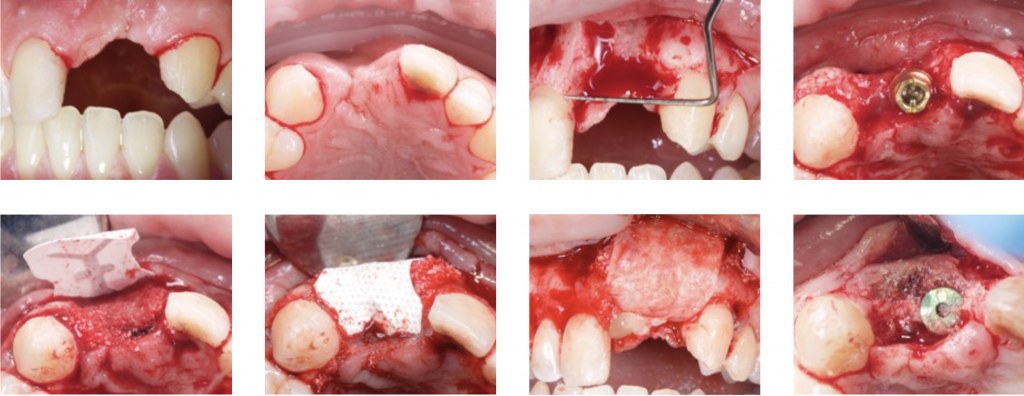

4) DEHISCENCE- TYPE DEFECT: CLASS 3

These defects are characterized by peri-implant dehiscences, in which the adjacent bone walls do not provide the volume stability of the area to be augmented.

In these defects, we will need support for the surrounding soft tissue to achieve stability of the grafted site. Reinforced e-PTFE membranes are mandatory.

Regeneration of class 3 defects step by step:

- Perforation of the cortical bone around the implant (Rompen 1999).

- Application of particulate bone substitute. Autogenous bone mixed with xenograft (50/50) has been reported as a reliable option to add potential osteogenic properties to the graft (Urban 2011).

- Resorbable membranes can be applied over the e-PTFE membrane to facilitate spontaneous wound healing during soft-tissue dehiscence.

- Sutures should be adapted to allow submerged healing.

- De Stavola showed minimal tension (less than 5g) on the flap margins and did not interfere with

primary wound closure.

More tension means more risk and significant complications, so De Stavola proposes a Suspended External-Internal suture (SEI) to reduce marginal flap tension after bone reconstruction (Stavola 2014).

The suture involves only the inner part of the buccal flap to avoid the “killer loop effect.”

After a horizontal mattress and simple suture are performed.

- If we seek a vertical gain, a staged approach is recommended: first regenerate and then place the implants (Artzi 2010).